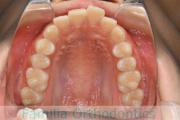

No.22V-409

- 主な症状:

- 叢生

- 年齢:

- 16歳

- 性別:

- 女性

- 抜歯部位

- 上:

- 44

- 下:

- 8|58

- 主な使用装置:

- FEA

- 治療にかかった費用:

- 86万円

八重歯を治したいということで来院されました。下あごの左ずれのある上顎前突(出っ歯)・叢生(でこぼこ)でしたので、上は左右から、下はで左のみ小臼歯を抜歯して、歯科矯正用アンカースクリューとマルチブラケット法にて治療を行いました。2年強、30回程度の通院が必要でした。

上下とも前歯の叢生(でこぼこ、凹凸、ガタガタ)があるため、保定を怠ると後戻りのリスクがあります。